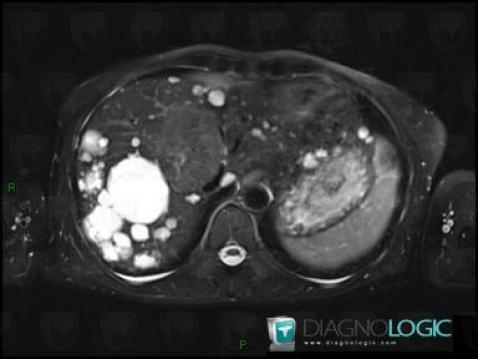

Hyperplasie nodulaire focale, Foie, IRM

Voici les informations spécifiques à l'image clé ci dessus:

- Diagnostic Hyperplasie nodulaire focale, Localisation(s) Foie, comportant les gammes Lésion hépatique en hypersignal T2

Polykystose rénale, Foie, IRM

- Diagnostic Polykystose rénale, Localisation(s) Foie, comportant les gammes Lésion hépatique en hypersignal T2

- Diagnostic Polykystose rénale (lié à Polykystose hépatique), Localisation(s) Foie, comportant les gammes Lésion hépatique kystique